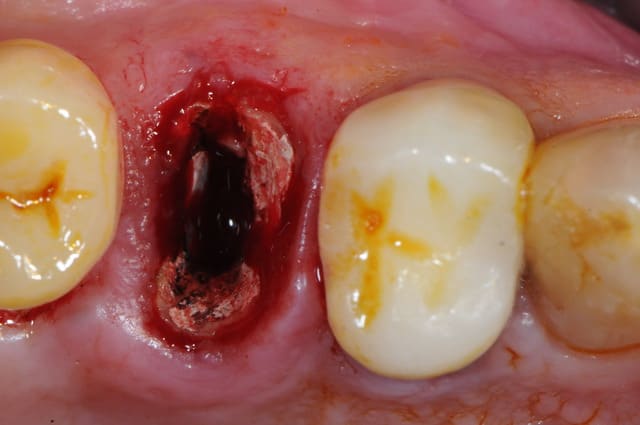

ton intervention, albert, me rappel un cas clinique que j'aimerai partager avec vous:

1-2-3 prémolaire foutu juste à proximité d'un implant, faut donc faire gaffe aux tissus environnant.

en plus je suis sure que la corticale vestibulaire est K.O elle aussi.

4-5: eh ben oui, elle est détruite! une simple curette insérée dans l'alvéole permet de visualiser l'importance de la perte osseuse vestibulaire.

que faire ??

1- curette en appuie sur la face vestibulaire montrant la destruction osseuse.

2- lambeau pleine épaisseur en palatin pour aller chercher un bout de conjonctif qui soit pédiculé.